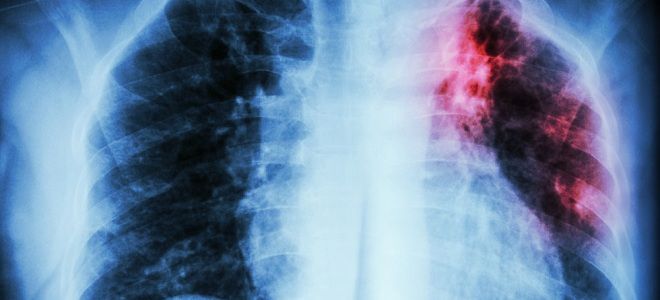

Очень опасное заболевание – туберкулез. Хроническая болезнь поражает дыхательные пути и способствует формированию очагов некроза в легких с летальным исходом для больного. Возбудитель из внешней среды попадает в организм воздушно-капельным путем, реже источником инфекции являются домашние животные (рогатый скот).

Поскольку бацилла Коха проникает в легкие и поражает некогда здоровые ткани, при туберкулезном поражении требуется выполнение флюорографии. Такое клиническое обследование не способно определить типы микобактерий, зато отчетливо выявляет существующие формы туберкулеза. При наличии опасных форм заболевания необходим курсовый прием противотуберкулезных препаратов. Больным туберкулезом легких дополнительно показан анализ мокроты, чтобы понять типы палочки, способной вызывать рецидив.